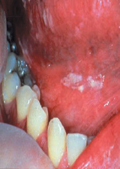

Herpes Type 1

Herpes type 2